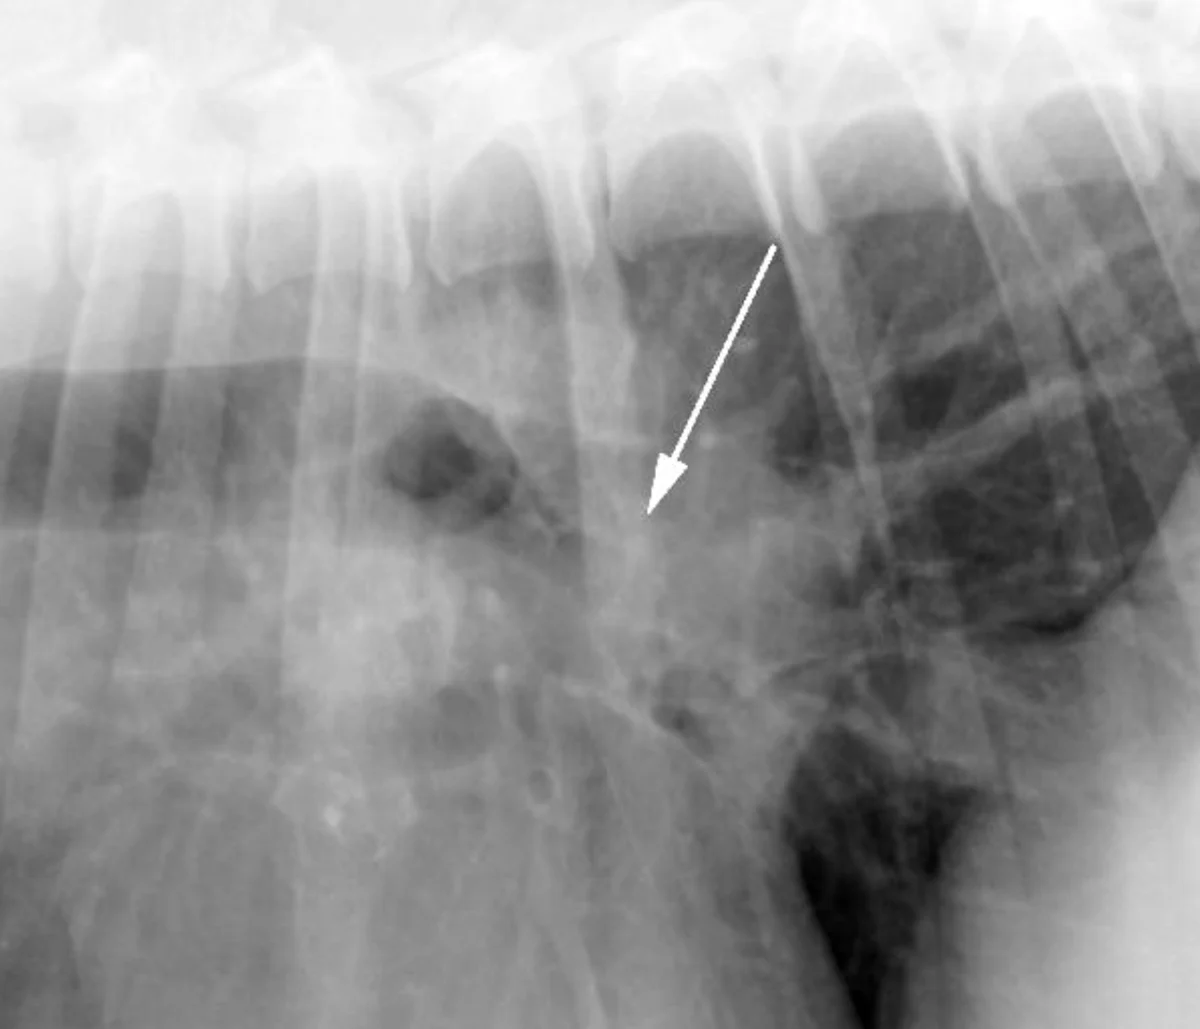

Extrapleural sign (arrow) in a 10-year old basset hound, secondary to the enlarged costochondral junctions and medial deviation of the costal cartilages